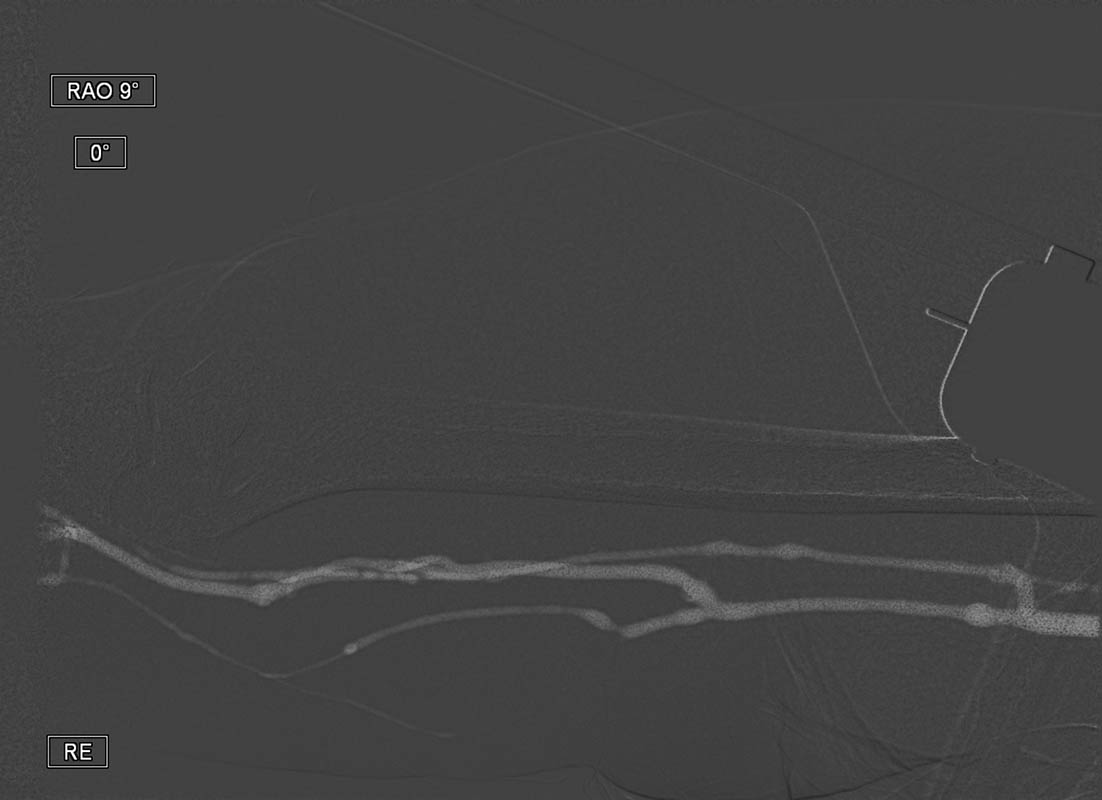

Sie möchten sich einen ersten Überblick über unser Produkt, dem CO2 Injektor Inspect 3005R verschaffen?

Nachfolgend haben wir eine Reihe Infomaterial über denKontrastmittelinjektor (Kontrastmittelpumpe) für die CO2 Angiographie zusammengestellt.

Nachfolgend haben wir für sie eine Reihe Publikationen / Links über das Thema CO2 Angiographie zusammengestellt.

Es gibt aktuell über 450 Publikationen zum Thema CO2 Angiographie.